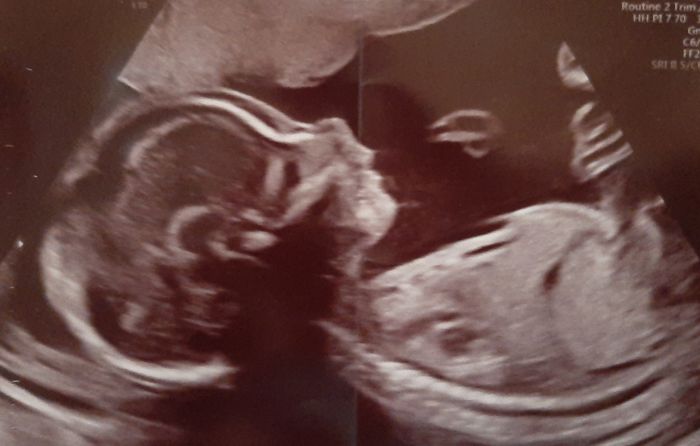

Holky tak mam po 2 screnu....vse vypada v poradku avsak ty panvicky co meli v 16 tydnu 3,5 mm maj ted 5,1 a 5,5

Takze je pravdepodobne ze jak mimco poroste porostou i ty panvicky...budou pozorovat a merit ty panvicky kazdy mesic tak uvidime no...kazdopadne prcek ukazoval na mereni palec nahoru

Bublinko, nádherná fotka!

krásné miminko